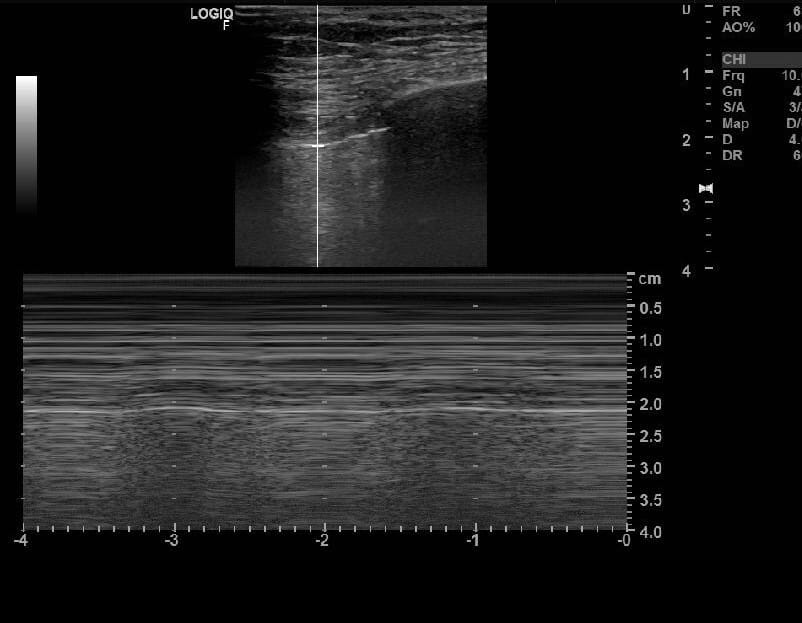

초음파 소견

응급 상황에서 빠르게 기흉을 진단하는 데 유용.

| 초음파 소견 |

| 🔵 폐활동 소실(Absent lung sliding): 정상적인 폐 움직임이 보이지 않음. |

| 🔵 바코드 사인(Barcode sign): M-mode에서 정상적인 파도 모양이 아닌 바코드 형태로 보임. |

| 🔵 폐 점프 사인(Lung point sign): 정상 폐와 기흉 부위의 경계를 확인 가능. |

기흉의 초음파 소견 (M-mode)

- Seashore sign : 정상 소견 , 파도 모양 (~~~)

- Barcode Sign : 비정상 소견, 바코드 모양 (===)